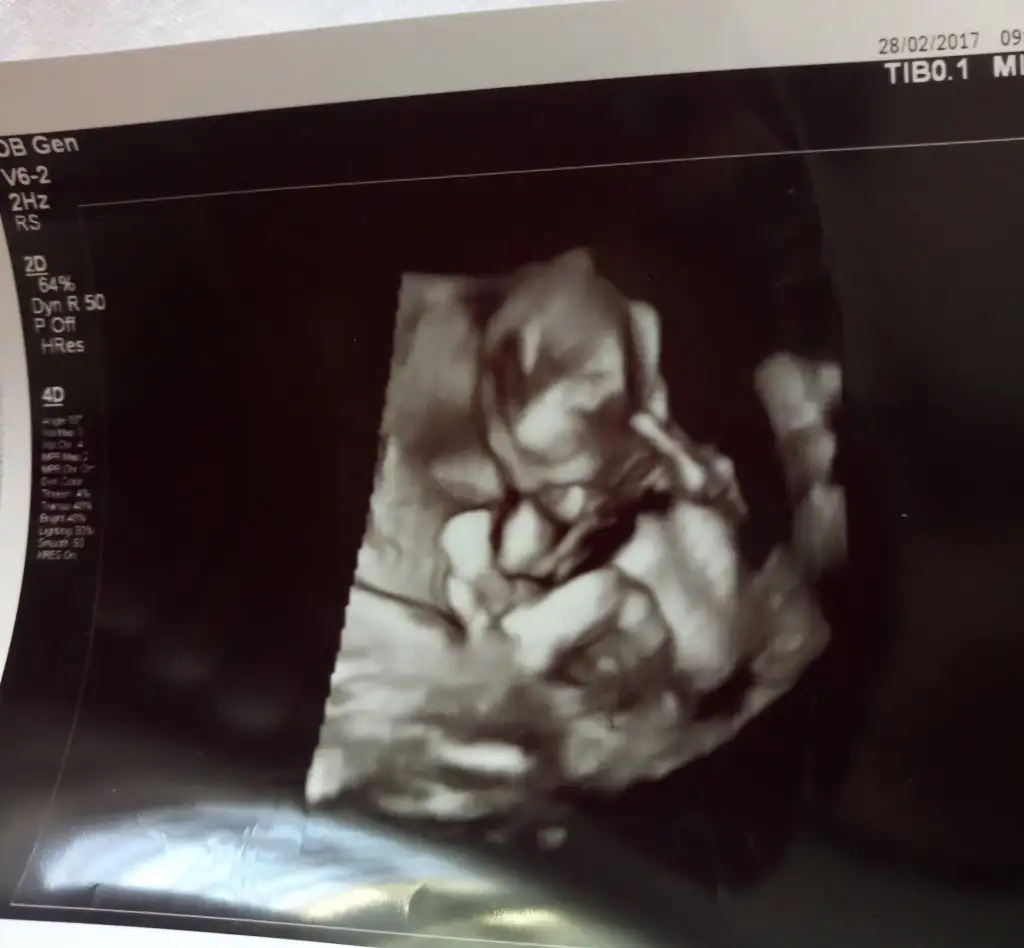

Cinsiyetini öğrendiğimiz gün oglumun ultrason fotoları alnı çıkıntılı mı anlayamadım tam ama bacak arasındaki çıkıntı ben burdayim demiş

ay bizde böyle görmüştük büllüğü tabak gibi meydandaydı